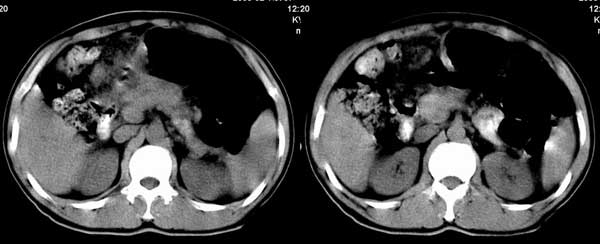

以下是引用听蝉观竹在2005-2-15 23:30:28的发言:[br]胃窦癌。[br]建议做胃镜检查并活检。